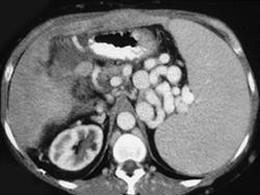

问题 男,50岁,患乙肝多年,现腹胀,右上腹痛,消化不良,消瘦、乏力、贫血、黄疸,血清转氨酶升高,白蛋白/球蛋白比值倒置。CT检查如下图,最可能的诊断是 ( )

选项 A、肝硬化、门脉曲张、脾大 B、肝硬化、脾大 C、肝硬化、腹膜后淋巴结肿大 D、肝硬化、肝癌、腹膜后淋巴结肿大 E、肝硬化、肝癌

答案 A